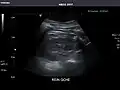

Renal ultrasonography

Ultrasonography of the kidneys is essential in the diagnosis and management of kidney-related diseases. The kidneys are easily examined, and most pathological changes in the kidneys are distinguishable with ultrasound.[7]

Kidneys: Right and left kidneys measure 11.5 cm and 12 cm in length respectively. No hydronephrosis. Small left lower pole kidney cyst.

Right kidney